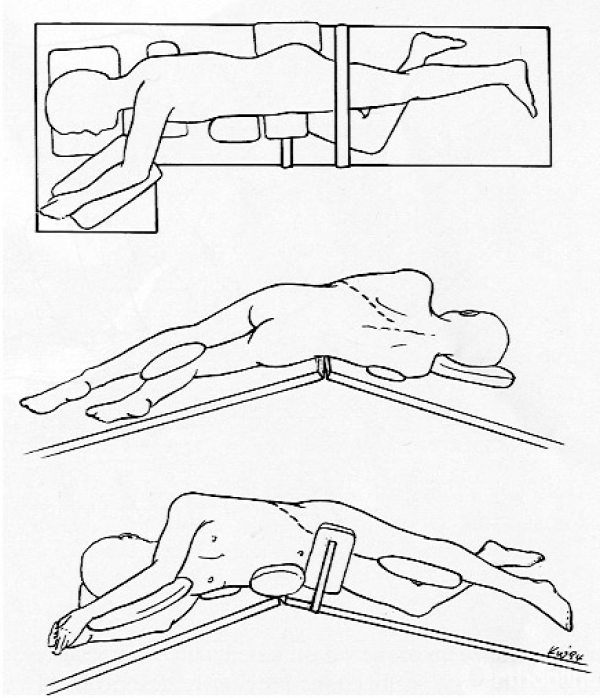

胸腰段/腰段AIS前路矫正术体位摆放

患者呈侧卧位,凸侧朝上。将患者固定于手术床上,侧凸顶椎位于手术床中央,并于凹侧垫衬垫或将手术床折叠形成腰桥。腋窝下应垫软垫防止压迫上肢神经。

图11.前路矫正术体位摆放示意图